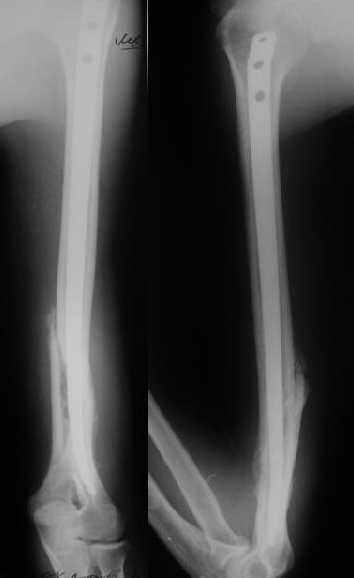

>антероградный - 30 процентов имеют боль в плече, связанную с повреждением ротаторной манжеты

Мы в последние годы все еще используем для переломов такой локализации эластичные титановые стержни (по мотивам ярославских разработок, Зверева-Ключевского). Такой стержень можно вводить не через сухожилие надостной мышцы, а дистальнее.

Снимки до, через 1 и 2 мес. после синтеза.